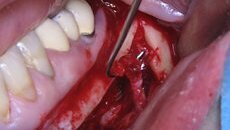

Osteotomické koncovky používáme pouze k separaci zubních tkání, které budeme závěrem extrahovat. S výhodou pro situace, kdy plánujeme okamžitou implantaci, je provedení extrakce pomocí piezochirurgie, ne však způsobem, který je často demonstrován na různých školeních a workshopech. Tam bývá stomatologům často doporučováno použití extrakční koncovky místo periotomu. To může vést k přehřátí okolní kosti a následným komplikacím ve smyslu alveolitis sicca. Extrakce v těchto situacích by měla být provedena jako postupná separace kořene a jeho odstranění po částech, přičemž okolní kostní tkáně se snažíme dotýkat minimálně, abychom nepoškodili kostní buňky zubního lůžka.

Stále častěji jsou na naši kliniku doporučováni pacienti, u nichž došlo k trvalé ztrátě citlivosti oblasti dolního rtu a brady nebo naopak neuralgiformním bolestem nervus alveolaris inferior v důsledku jeho poranění při implantaci nebo chirurgické extrakci retinovaného zubu. V těchto případech provádíme deliberaci tohoto nervu buď z přístupu ze sagitální osteotomie mandibuly nebo pomocí piezochirurgie. Následně odstraníme amputační neurom a nerv mikrochirurgicky rekonstruujeme (obr. 5a, 5b).